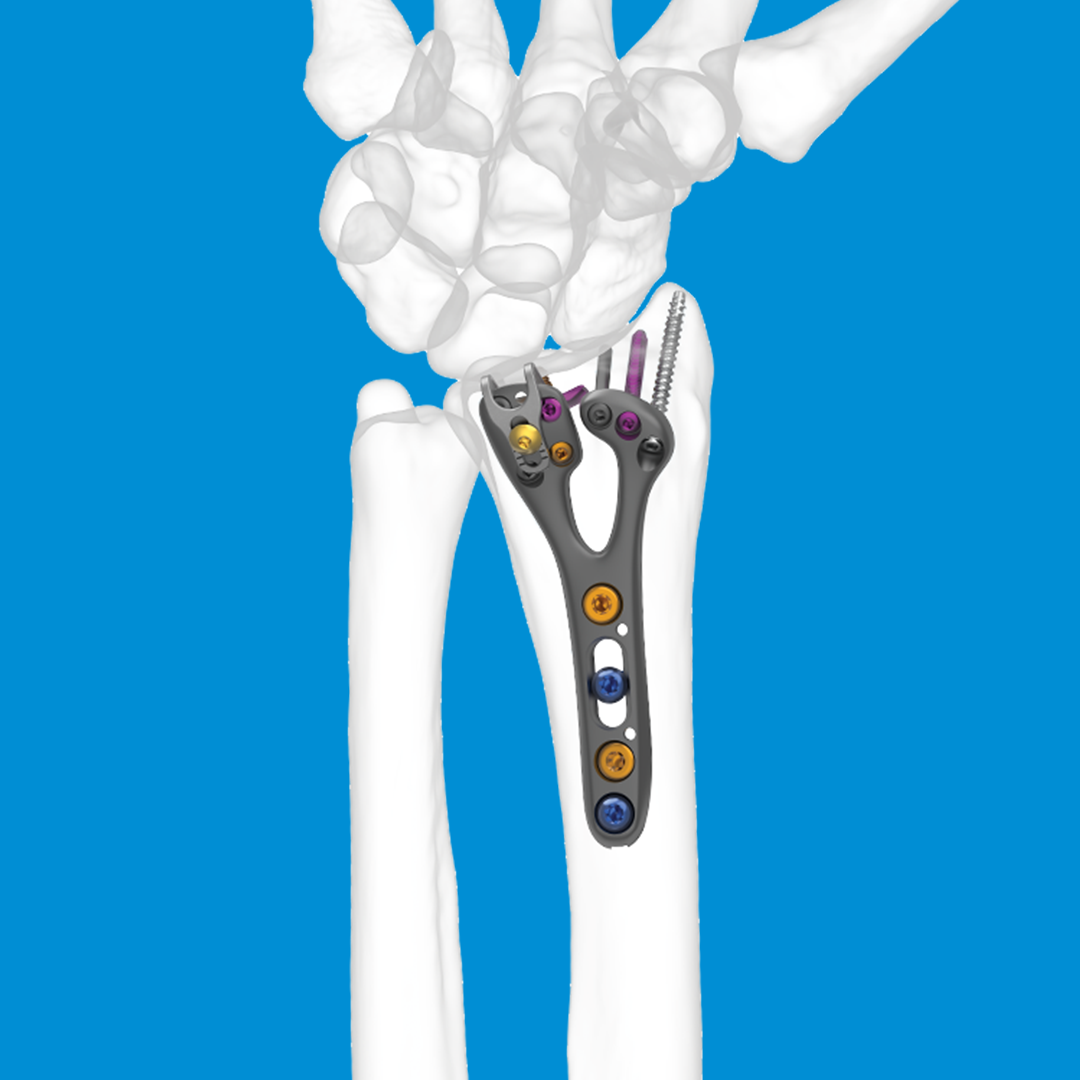

IMPLATE® Wrist Arthrodesis Nail

- Intramedullary wrist arthrodesis system

- Minimally invasive fusion nail provides a strong, stable construct tailored to the functional needs of the patient.

- Placement of the intramedullary device minimizes irritation to the soft tissue

Intramedullary placement minimizes soft tissue irritation

IMPLATE® Wrist Fusion Nail